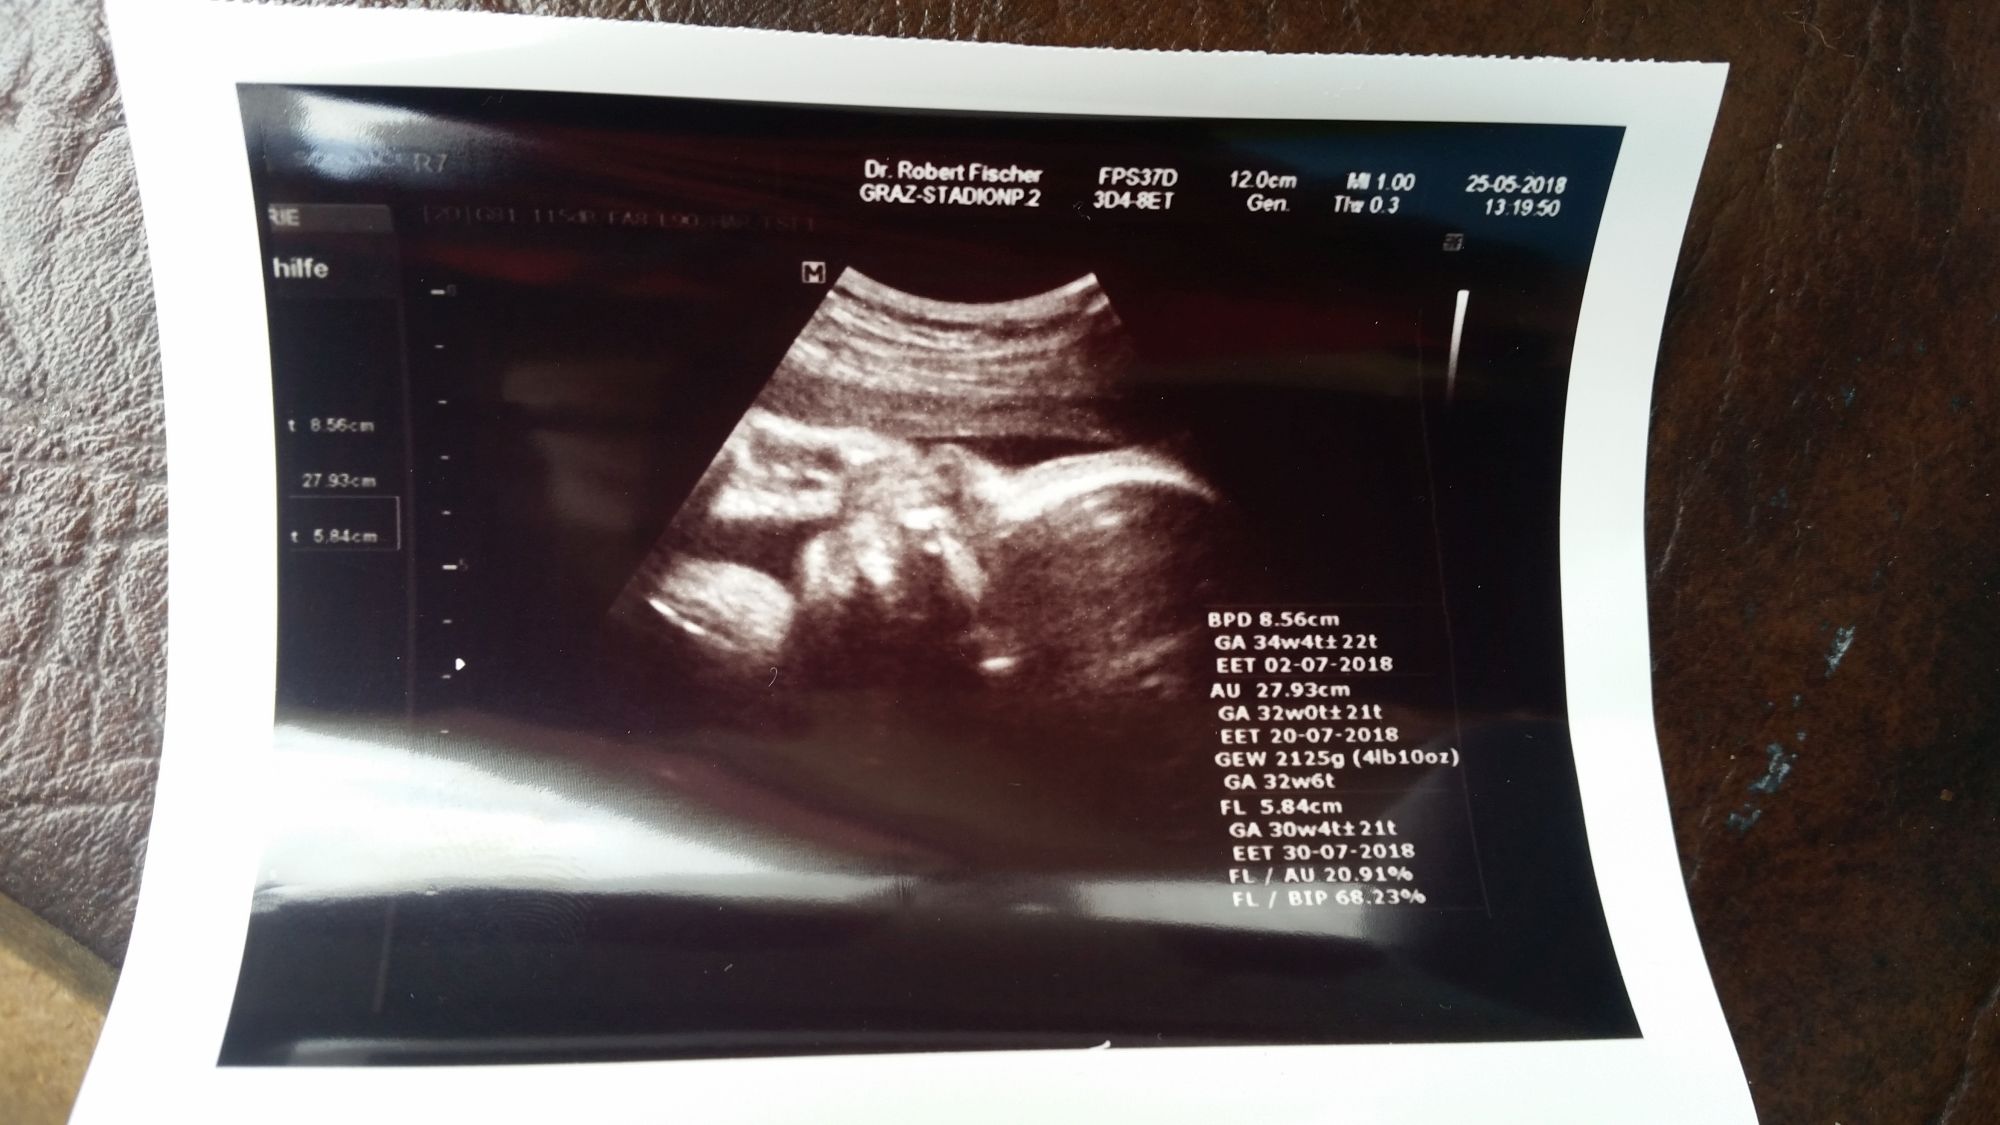

Nach dem Gesang tuckern wir weiter nach Graz und übernachten bei einem Systema-Kampfkunstfreund von uns. Spätnachts ankommen, übernachten und dann Jamsession mit Gitarre und Akustischem Bass inklusive Frühstück im Garten und Hundeakrobatik. Danach ab zum Frauenarzt, Standard-untersuchung. Alles super in Ordnung. Mittlerweile hat unser Zwergi nach Messungen des Arztes 2125 Gramm. Blick auf das Röntgenbild zeigt Daumen bzw. Hand im Mund, dann muss alles in Ordnung sein, denk ich mir.